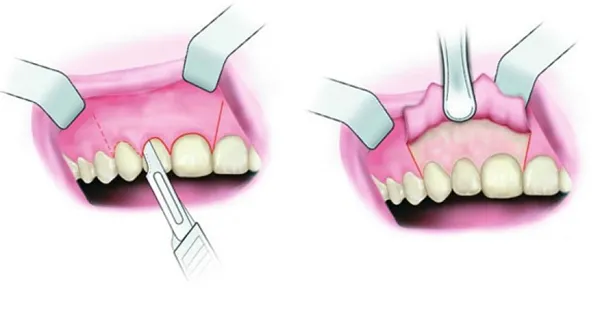

Cắt lợi là một kỹ thuật nha khoa được thực hiện để hạn chế các bệnh liên quan đến lợi. Những trường hợp như hở lợi, viêm